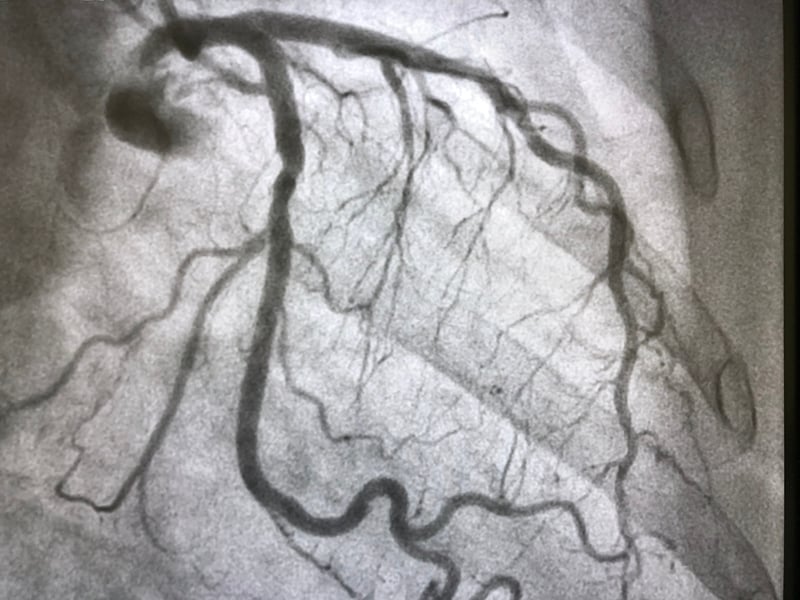

Coronary artery disease (which affects the vessels supplying blood to the heart) is caused by atherosclerosis—a pathological thickening of the arterial walls, resulting from various factors that lead to the formation of plaques that grow due to fat accumulation, inflammation, and other pathophysiological processes.

When these atherosclerotic plaques rupture or detach, they can suddenly block the coronary arteries, interrupting blood flow to the heart and causing the death of part of the cardiac muscle—this is what we call a myocardial infarction (heart attack).

“Today, a patient suspected of having coronary disease undergoes a CT scan (Computed Tomography) to observe the state of the vessels and measure the degree of stenosis (that is, how much they have narrowed). This assessment helps determine whether the patient has ischemia, a reduction in blood flow to the heart during periods of increased demand, such as during everyday physical effort.

This is also important for understanding the likelihood that the patient might have a heart attack in the near future. However, while measuring stenosis is very useful, it is not sufficient for accurate prediction. One of my research projects aimed to use AI to automatically extract additional quantitative information from CT scans — beyond stenosis — data that can reveal much more about the pathophysiological processes occurring within the artery walls. AI can extract and analyze this information to predict the risk of heart attack for each individual patient,” explains the Professor.